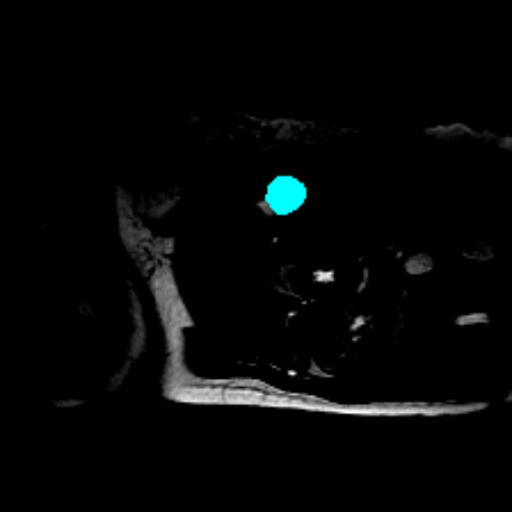

Figure 3 presents a qualitative comparison of segmentation performance on examples from the Synapse, BTCV, ACDC, and ISIC17 datasets. The first two examples (from Synapse) highlight variations in segmentation performance among U-Net, TransUnet, Mamba-Unet, and Swin-Unet. While Swin-Unet performs well in the first example, its performance decreases in the second example, particularly in segmenting the organ highlighted in blue. Additionally, it misclassifies background regions as the class highlighted in orange. In contrast, our approach demonstrates high robustness in segmenting all classes accurately and aligning well with the ground truth masks.

Across BTCV, ACDC, and ISIC17, the comparison methods exhibit varying performance depending on the task and class. For instance, Mamba-Unet struggles to segment multiple organs in BTCV, even misclassifying certain classes as others. In the ACDC dataset, both TransUnet and Mamba-Unet perform poorly in segmenting the three classes. In the last column (ISIC17), Swin-Unet oversegments the skin lesion compared to the ground truth. Unlike the comparison models, our approach consistently delivers effective segmentation across different tasks and datasets.

These qualitative findings further reinforce the quantitative results presented in the experimental section, demonstrating the effectiveness of our MambaCAFU model in handling binary and multi-class segmentation across diverse medical imaging modalities and tasks.

Slice GT Unet TransUnet Mamba-Unet Swin-UMamba MambaCAFU-V1

Figure 3: Visual comparison of segmentation examples from Synapse (first two examples), BTCV (3-4 examples), ACDC (5th example) and ISIC17 (last example). Columns: input slice, ground truth, Unet, TransUnet, Mamba-Unet, Swin-UMamba, and MambaCAFU-V1.